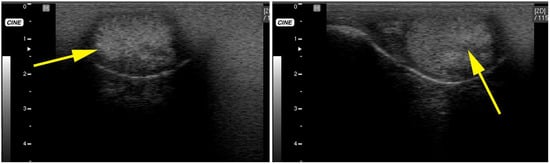

3.3. Testicular and Epididymal Cysts

- Bott, I.; Pearson, L.K.; Rodriguez, J.S. Prevalence and Pathologic Features of Rete Testis Cysts in Alpacas (Vicugna pacos). Clin. Theriogenol. 2010, 2, 395. [Google Scholar]

- Barrios, S.W.; Chavera, C.A.; Huamán, U.H. Testicular Anatomo-Histopathological Alterations in Alpacas (Vicugna pacos) Slaughtered in Nuñoa, Puno. Rev. Investig. Vet. Perú (RIVEP) 2011, 22, 223–232. [Google Scholar]